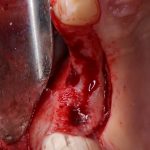

Для получения костного блока, мы открываем донорскую зону, наружную косую линию нижней челюсти.

Получение костного аутотрансплантата.

Здесь потребуется пародонтологический зонд с миллиметровой разметкой или какой-то другой измерительный прибор (операционная линейка). Ранее по КЛКТ я измерил костный дефект, теперь нужно нанести границы будущего костного блока на донорскую зону.

Для получения костного блока мы использовали ультразвуковую пьезохирургическую систему. Это самый удобный и безопасный инструмент для проведения подобных манипуляций. С помощью него мы сформировали и выделили костный блок. Он должен отделяться легким движением остеотома или элеватора. Как это сделать правильно — читай здесь>>

Подготовка костного ложа и фиксация аутотрансплантата

Возвращаемся к основной операционной области. Еще раз посмотрим на альвеолярный гребень, поофигеваем от его ширины и моих грандиозных планов: